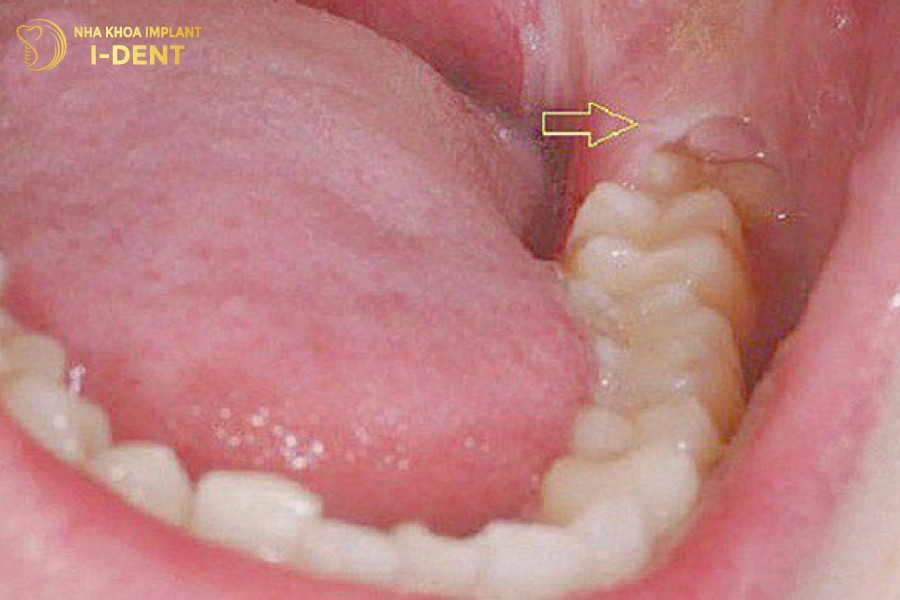

1.5 Răng mọc kẹt trong niêm mạc miệng (lợi trùm răng khôn)

Đây là tình huống tạo ra nhiều cảm giác đau nhức, khó chịu nhất cho người bệnh. Răng khôn khi mọc không thể trồi lên trên, nằm kẹt trong niêm mạc. Trong tình huống này, người bệnh sẽ bị sưng nướu, kèm áp xe, đau đầu, nóng sốt,…

Lợi trùm răng khôn